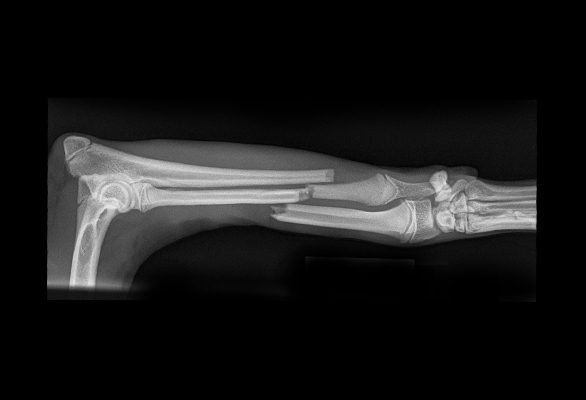

A full understanding of the injury is needed before a decision can be made on how best to manage it. This information is gathered by taking radiographs or by performing a CT scan.

In some cases, fractures can be managed without surgery, and support bandages or casts are used. Most patients with fractures do benefit from surgery since this often allows early weight bearing through the leg. This tends to make them more comfortable and better able to maintain their muscling and joint movement. They are also easier to look after if a large support dressing hasn’t been used.

Surgery aims to realign and stabilise the fractured bones to allow uneventful healing. There are numerous methods used to stabilise the fractured bone including the use of plates, screws, pins, and wire. These are hidden from view and placed under the skin (internal fixation).